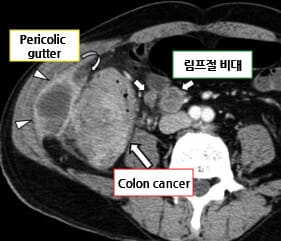

CT 소견 (Contrast-enhanced CT)

🔵 장벽 비후 (Bowel wall thickening)

암 부위의 장벽이 국소적으로 두꺼워지며, 조영증강되는 불균일한 덩어리로 관찰됩니다.

🔵 림프절 종대

단일 또는 다수의 림프절이 비대해져 전이 가능성을 시사합니다.

Kim, S. W., Shin, H. C., Kim, I. Y., Kim, Y. T., & Kim, C.-J. (2010). CT findings of colonic complications associated with colon cancer. Korean Journal of Radiology, 11(2), 211–221. https://doi.org/10.3348/kjr.2010.11.2.211